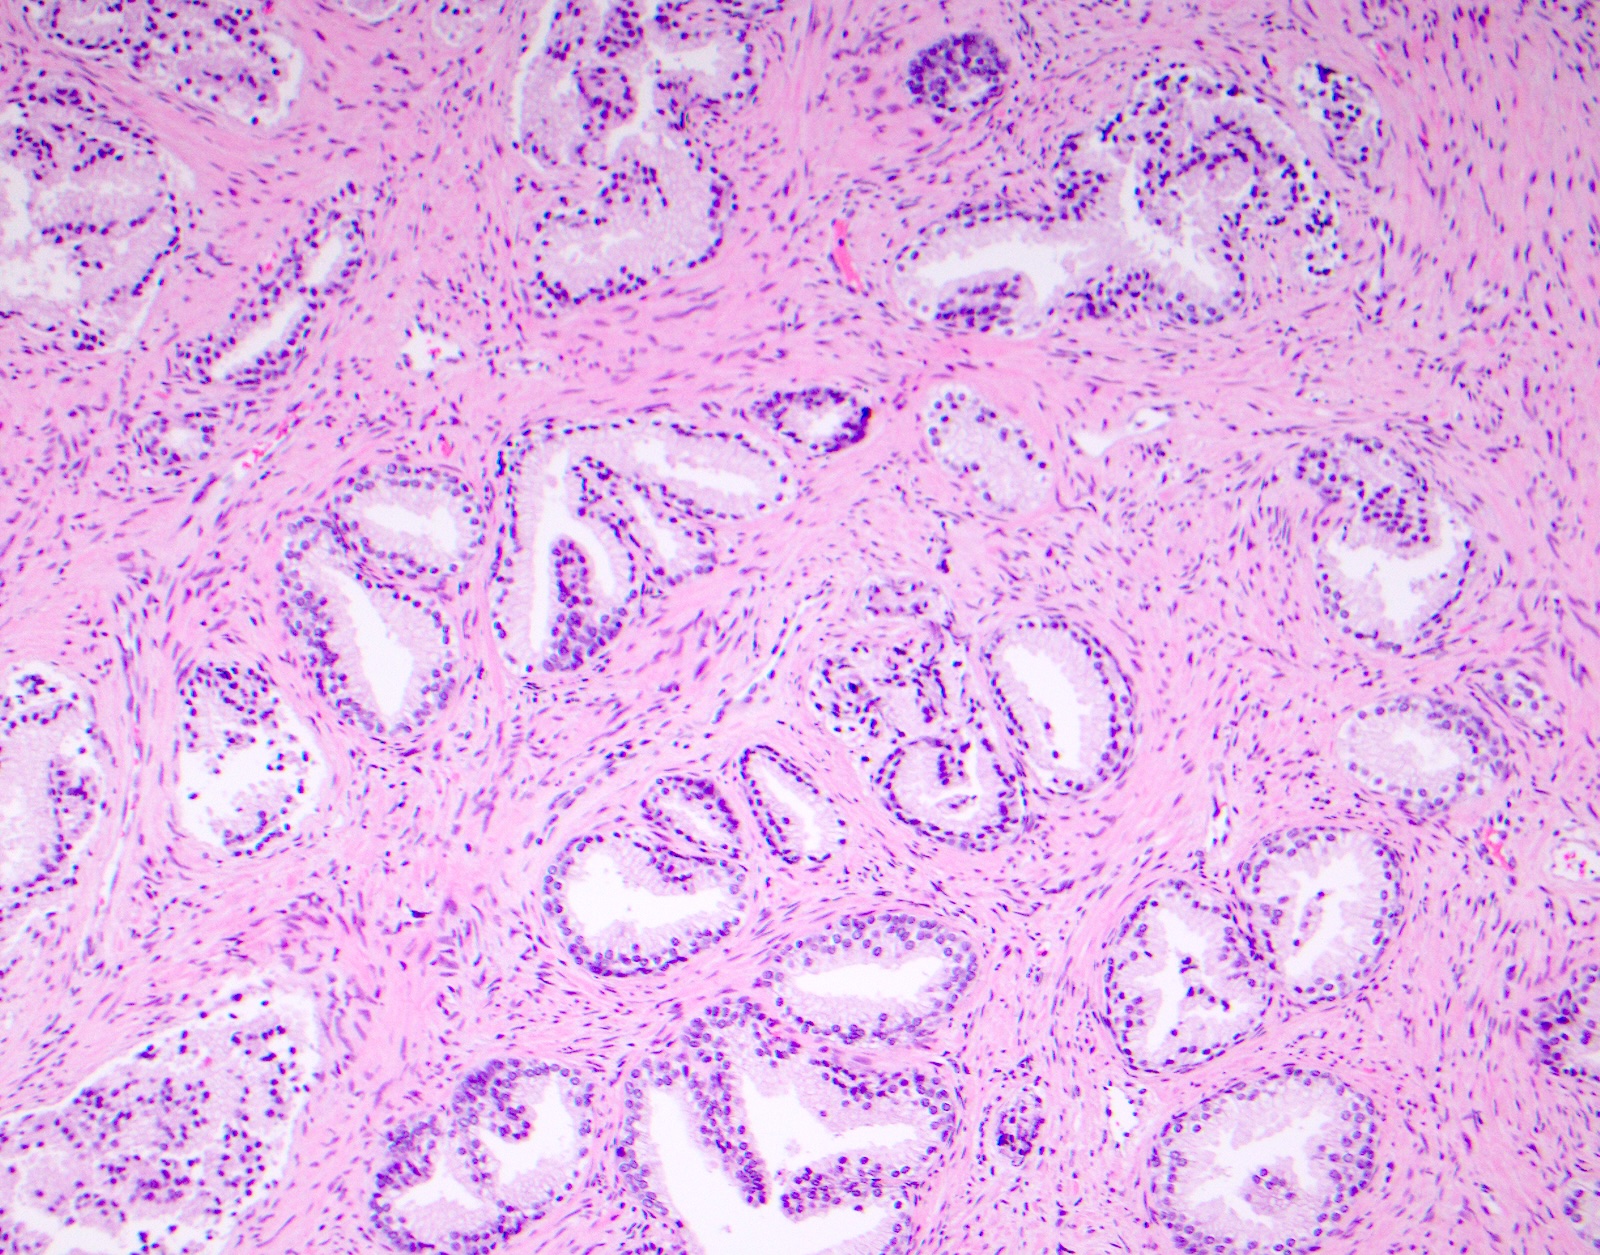

Microscopic (histologic) images

Contributed by Surekha Bantumilli, M.D. and Dimitri G. Trembath, M.D., Ph.D.

- Breast intraductal lesions

- 90% of flat epithelial atypia, atypical ductal hyperplasia and ductal carcinoma in situ are negative to focally positive for 34βE12

- In contrast, all cases of usual ductal hyperplasia and 90% of lobular carcinoma in situ (LCIS) are diffusely positive with perinuclear cytoplasmic staining with 100% of classic lobular intraepithelial neoplasia exhibiting this pattern (Am J Clin Pathol 2018;149:S30, Arch Pathol Lab Med 2014;138:1629)

- Florid ductal hyperplasia without atypia (intense staining) (Am J Surg Pathol 1999;23:1048)

- Breast ductal hyperplasia and lobular intraductal neoplasia (J Histochem Cytochem 2003;51:1527, Am J Surg Pathol 1999;23:1048)